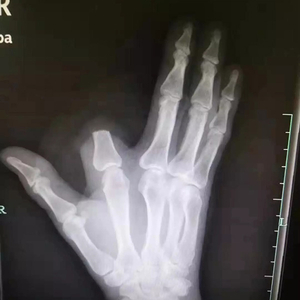

“打开一看,我们发现患者的食指少了一大截。”袁丞达一问,张先生颤抖着回答:“砍了,保命要紧!”

原来,被咬后,张先生仔细一看,发现伤人的是条剧毒五步蛇,怕自己走动后毒性发作,一时恐惧紧张,就拿刀将自己的食指斩断了。事后,他将断指就地丢弃,没有一并带到医院。

检查结果出来,张先生的凝血功能正常,医生为他注射了抗蛇毒血清。本来,断指尚可以再植,如今,只能由骨科医生手术处理断指残端,张先生也将留下终身残疾。